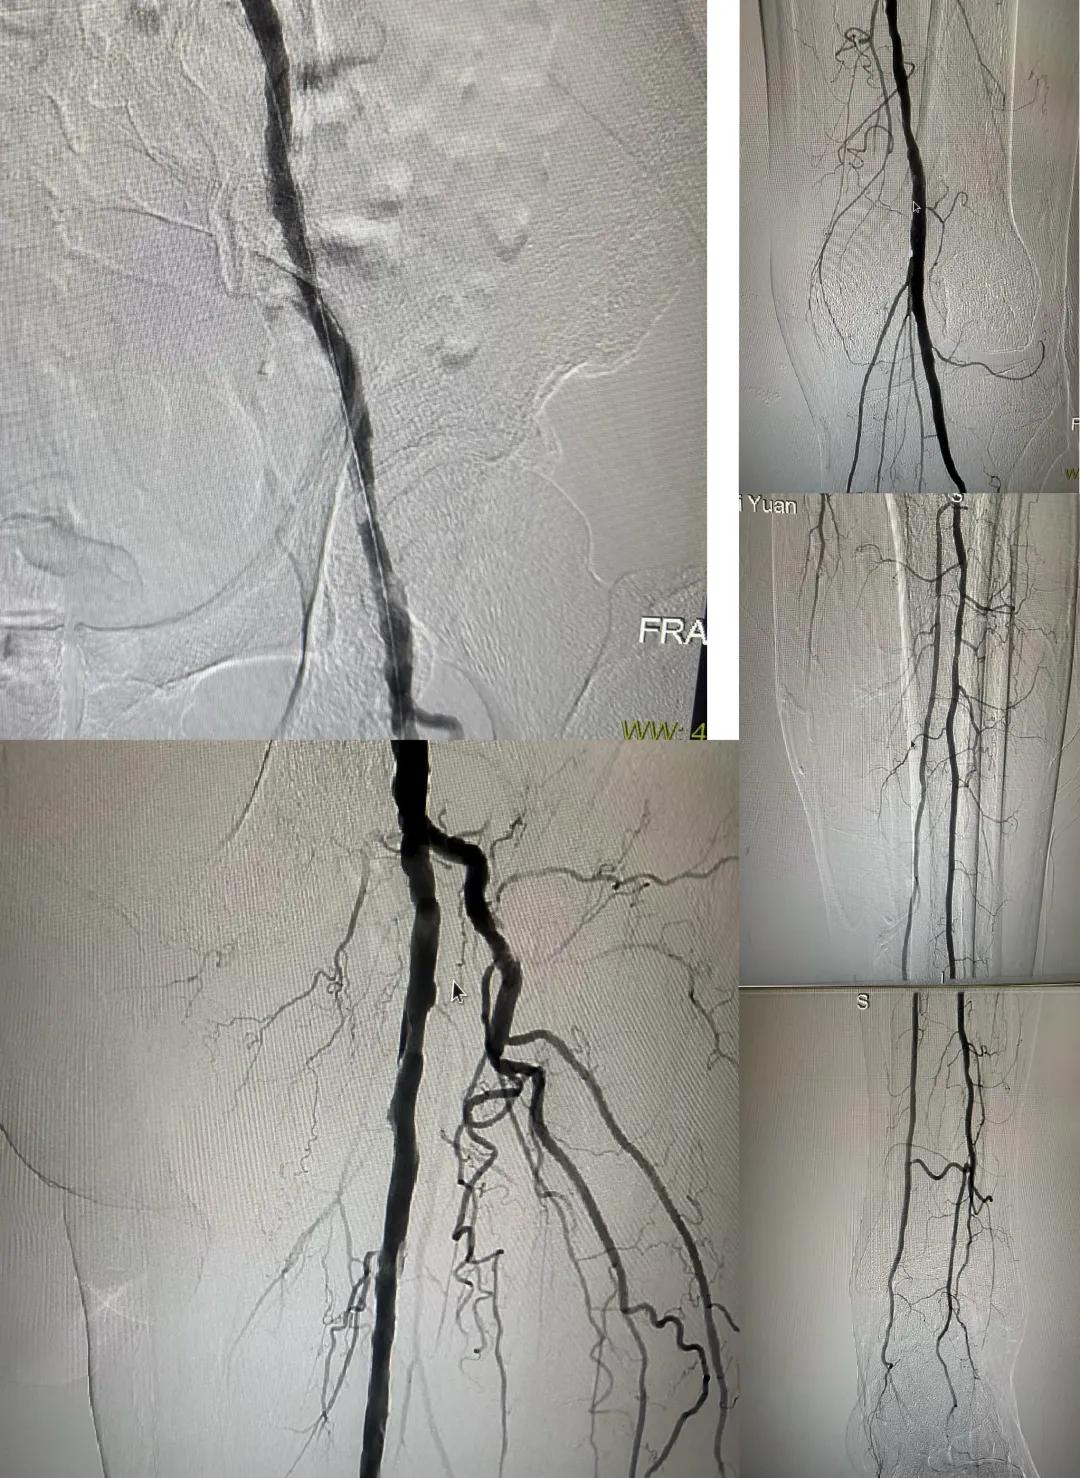

患者,男,73歲,約15天前出現(xiàn)左側(cè)腳面腫痛,間歇性跛行,左足第三足趾壞疽,遂來市中醫(yī)院就診,以“下肢動脈硬化閉塞、糖尿病足壞疽、”收住外二科,評估患者病情后需實施左下肢球囊擴張成形術(shù)。術(shù)中造影見患者左側(cè)髂動脈、股淺動脈階段性重度狹窄。經(jīng)外周球囊擴張術(shù)后,再次造影見股淺動脈、髂動脈血流通暢,膝下及足部血流速度較前改善。

術(shù)后已疏通血管成像